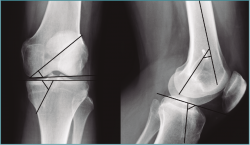

Figura 1. Angulación del túnel femoral en plano coronal, formada por la línea del eje del túnel femoral y la línea paralela a la superficie articular femoral en la radiografía anteroposterior y, en el plano sagital, formada por el eje del túnel y el eje de la diáfisis femoral, en la radiografía lateral. El ángulo del túnel tibial es el formado por la línea que pasa por el eje del túnel y por una línea paralela a la superficie articular tibial tanto en la radiografía anteroposterior como en la lateral.